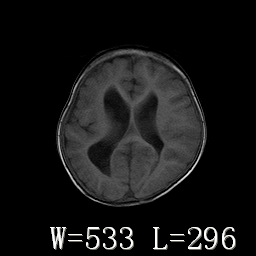

标题: PED3252:脑室增大。

女,3岁,3岁不会说话,阵发性抽搐、自伤。

考虑为梗阻性脑积水(中脑导水管狭窄)。

侧脑室不规则,前后角尖角样,脑白质较少:考虑灰质发育不良可能

倒数第3附图不是这个病人的吧!考虑脑白质发育不良可能。

右侧额叶发育不良!

右侧额叶发育不良。

右侧额叶发育不良

考虑,脑发育不良,胼胝体发育不全?(图片不全,矢状位?)